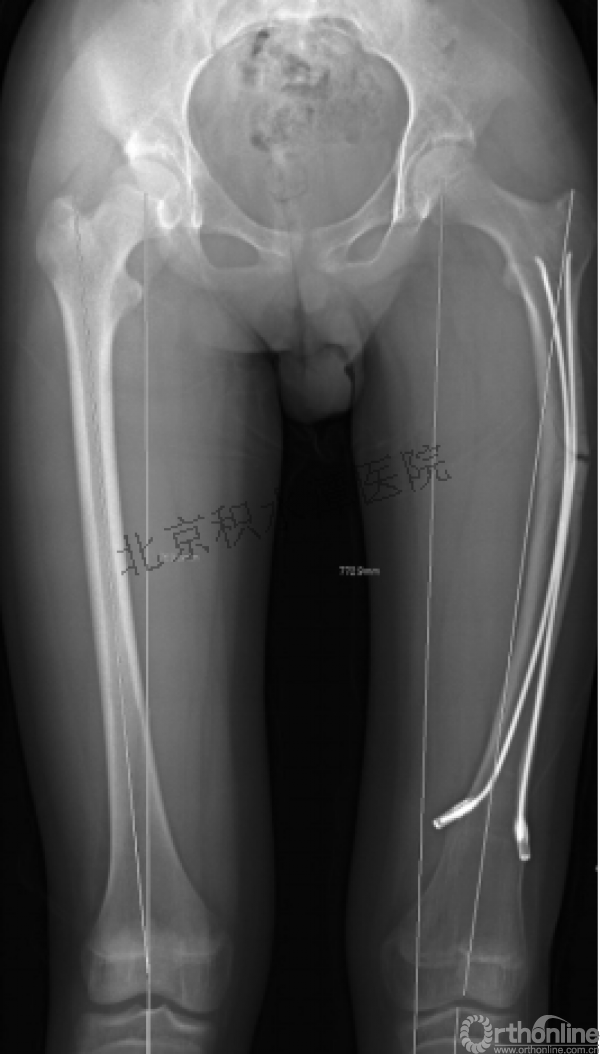

病例分享一

男孩 、5岁,初次骨折于2007年7月。

术后2年→再骨折→再次手术

钢板固定后一年

取板后再骨折→TEN

TEN取出后2个月

闭合复位再固定加尾帽

又过了4年!时间来到2015年

一年以后顺利愈合,实则危机四伏

数月后再骨折!牵引!

髋人字支具

外固定架术后一年

整整11年!是否治疗终结?